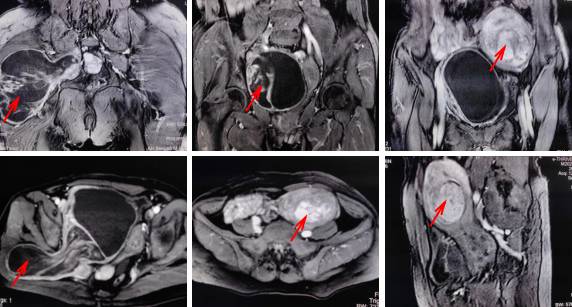

患者既往有肺部惡性腫瘤病史,雙側(cè)肺功能不全,發(fā)現(xiàn)盆腔及右側(cè)臀部腫塊2年余,病程中腫塊漸進(jìn)性增大。完善盆腔增強(qiáng)磁共振后顯示:右側(cè)盆腔囊實(shí)性腫塊經(jīng)坐骨大孔延伸至右側(cè)臀大肌肌間隙內(nèi),腫瘤大小約30 cmx15 cmx10 cm,有畸胎瘤的可能??紤]腫瘤橫跨盆腔及臀部,病變范圍大,已有膀胱壓迫癥狀,若不及時(shí)切除腫瘤,血管、神經(jīng)及盆腔臟器受累可產(chǎn)生不可逆損傷,醫(yī)護(hù)團(tuán)隊(duì)將患者緊急轉(zhuǎn)至骨科進(jìn)一步治療。

3月24日9點(diǎn),患者被推入手術(shù)室。麻醉科張運(yùn)淳主任醫(yī)師完成留置深靜脈置管、有創(chuàng)動(dòng)脈導(dǎo)管后立即進(jìn)行誘導(dǎo)麻醉、氣管插管,各種搶救藥品保證呼吸循環(huán)功能。術(shù)中周新社主任醫(yī)師及嚴(yán)曉波副主任醫(yī)師仔細(xì)分離瘤體保護(hù)周圍血管神經(jīng),見腫瘤沿閉孔向臀部生長(zhǎng),腫瘤組織與膀胱后壁粘連,泌尿外科代昌遠(yuǎn)副主任醫(yī)師仔細(xì)分離腫瘤粘連組織,避免膀胱損傷,術(shù)中沿前后切口分別分離后,完整取出大小約30 cmx15 cmx10 cm腫瘤組織;盆腔腫瘤取出后,在婦科郭祥瑞醫(yī)師協(xié)同下行子宮肌瘤切除術(shù),手術(shù)時(shí)長(zhǎng)3.5 h,比預(yù)計(jì)時(shí)長(zhǎng)縮短2 h,術(shù)中出血400 ml,考慮手術(shù)創(chuàng)傷較大,患者既往一般情況差,術(shù)后轉(zhuǎn)至重癥監(jiān)護(hù)室進(jìn)一步治療。